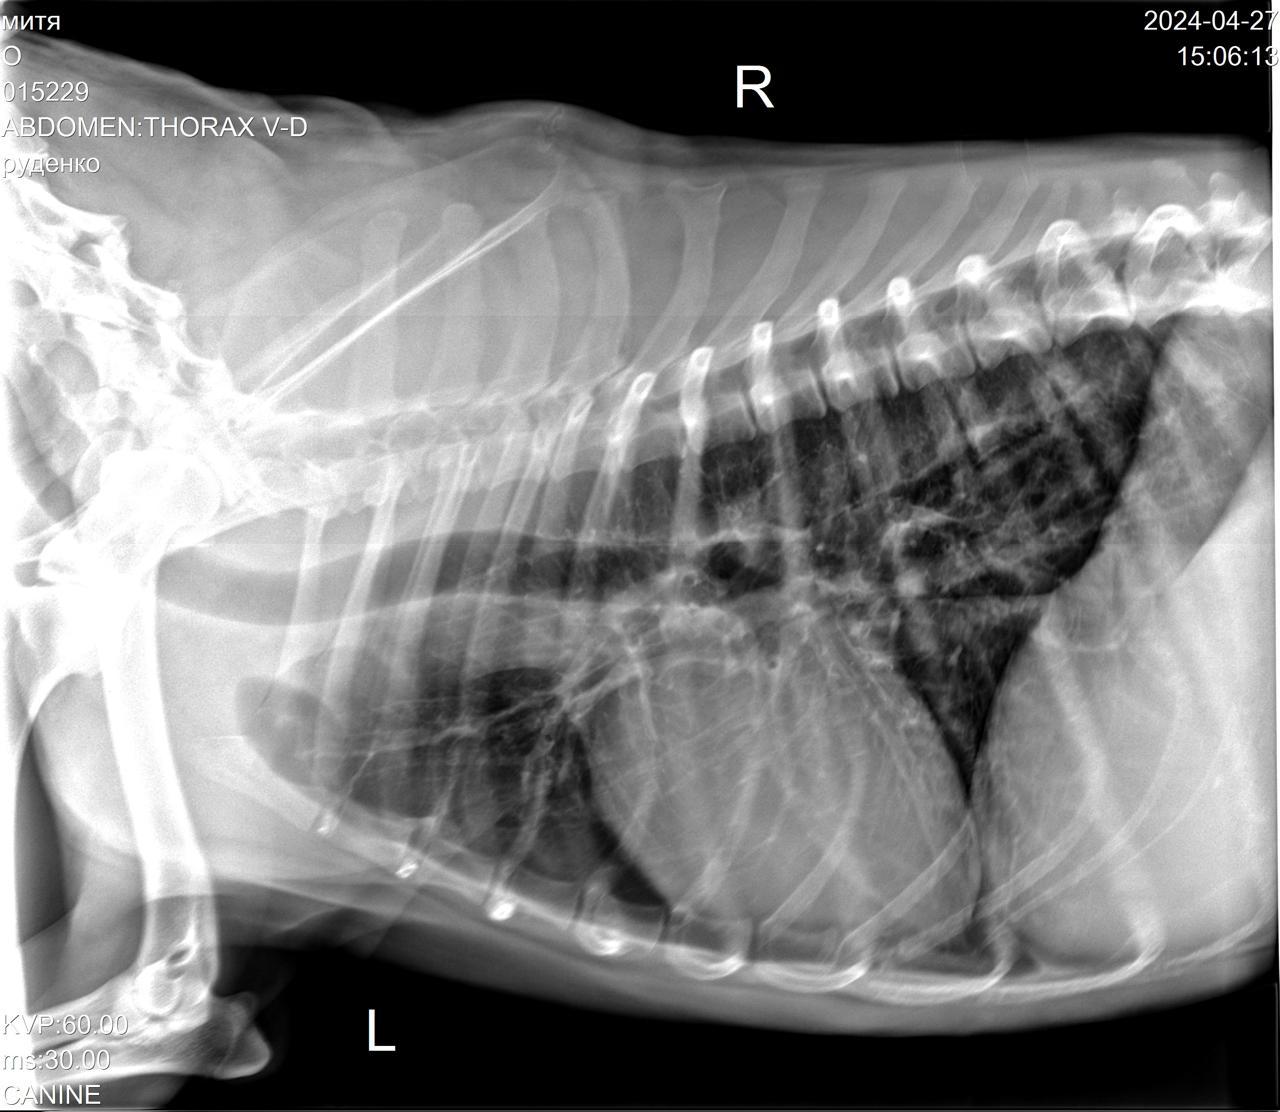

Сегодня Катюша возила Митю на рентген.

IMG-20240427-WA0028.jpg

IMG-20240427-WA0029.jpg

IMG-20240427-WA0030.jpg

IMG-20240427-WA0031.jpg

IMG-20240427-WA0032.jpg